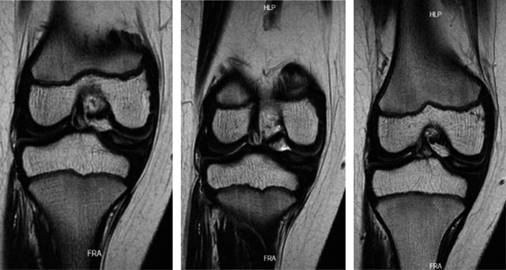

Se solicitó una resonancia magnética simple de la rodilla, que reveló una lesión de grado 3 en el menisco medial, bursitis suprarrotuliana y edema en los tejidos blandos de la parte anteromedial de la rodilla. Además, se identificó una lesión en el menisco medial con una morfología aparentemente discoidal, indicada por la presencia del «signo del corbatín» (Figuras 1 y 2).

Figura 2: Cortes coronales de resonancia magnética de rodilla derecha en secuencia T2 en los que se evidencia ligero aplanamiento del cóndilo femoral medial.